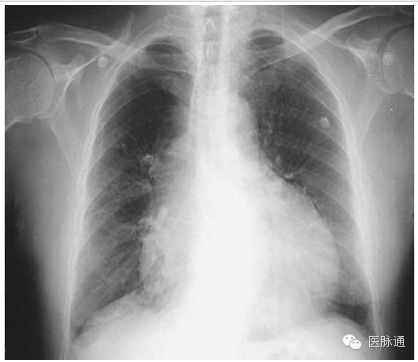

急性呼吸窘迫综合征定义为急性起病,PaO2/FIO2≤200 mmHg,胸片双侧浸润,以及肺动脉楔压≤18mmHg或无左心房高压的临床征象。胸片最常见的表现为双侧非对称性实变伴支气管空气征象(如图8箭头所示)。间隔线和胸腔积液并不常见。渗出期的早期表现是掩盖肺血管纹理的双侧实变。这些病变可演变为典型非对称的更广泛的弥漫性实变。在随后的纤维化阶段可能形成弥漫性间质。存活患者子啊10-14天后,多数影像学异常表现开始消散。

图8